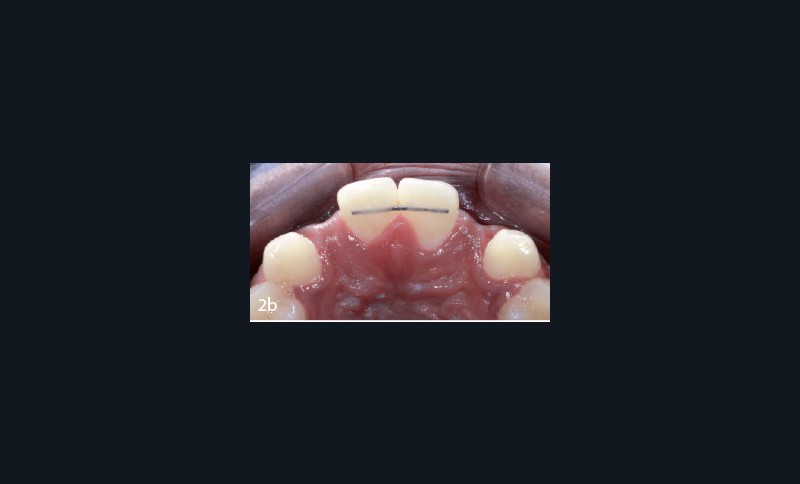

Un traitement multi-bracket est entrepris afin de fermer le diastème inter-incisif et de distaler les canines. Après deux ans et demi, devant un risque avéré de rhizalyse, la décision d’arrêter le traitement s’impose. L’ouverture des espaces est partielle et compatible avec les proportions cliniques souhaitées pour les deux incisives latérales (fig. 2a). Cependant, les orientations radiculaires de même que les largeurs de crêtes dans les deux secteurs édentés (fig. 2b) ne permettent pas d’envisager une reconstruction implanto-portée adéquate.